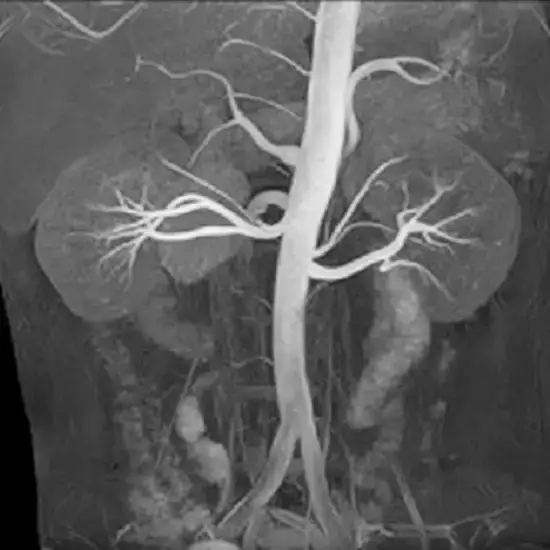

Magnetic Resonance Venography helps to visualize veins in the Kidney. This imaging test checks blood vessels which bring blood back from the kidney to the Lungs and Heart.

MR Renal Venography shows blood vessel abnormalities, blood clots, vessel tears etc.